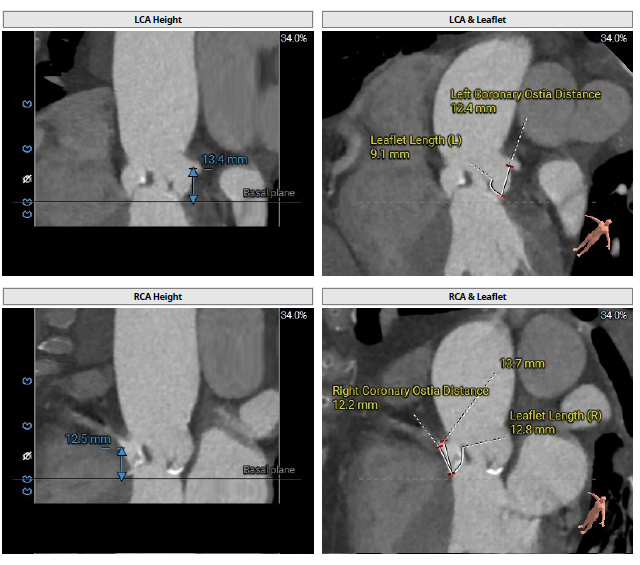

术前CT检查

冠脉开口高度可,右冠瓣冗长瓣叶,预估冠脉阻挡风险低术中密切关注冠脉血流灌注,必要时冠脉保护;